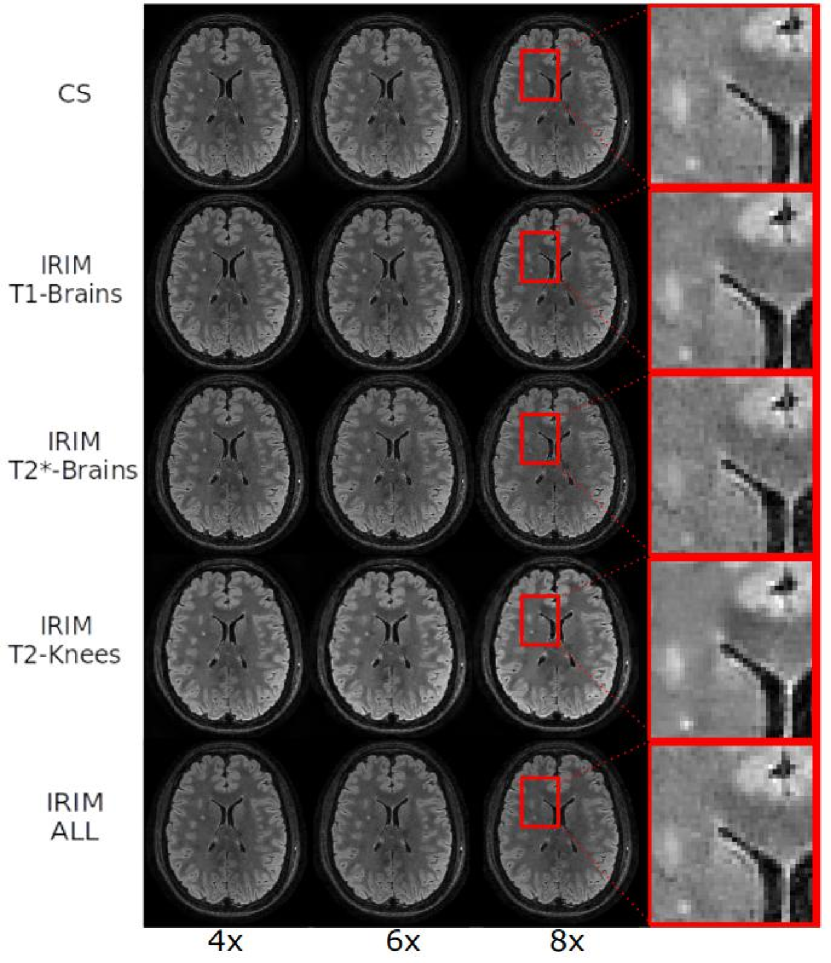

Fig. 4 depicts box-plots of the SSIM- and PSNR-scores for evaluating performance on different test sets (indicated in the graph headings). Each model was trained using the two loss functions (subsection 2.4) and different dataset compositions (subsection 2.5), as referred to at the top of the figure. For - and TSE brain data, the -norm resulted in a slight improvement in performance compared to the -norm. The -dataset appears to yield trained networks that generalize well to the other datasets. The network trained on -data does not perform well on the -data but it does show acceptable performance on the other datasets. Training on knee data results in clearly suboptimal results for all other modalities. Training on combined (ALL) datasets shows some generalization capabilities but does not yield the best performance. Overall performance of the models shows a preference for using the -norm as loss function over the -norm. CS approach generally performs worse than the RIM for all evaluation data and metrics, except for TSE-brains, where it shows a similar SSIM (but lower PSNR).

Fig. 5 shows the reconstruction images of one slice from the -weighted TSE brain dataset by each model trained with the -norm as loss function using the different training sets. Observe that the less complex MRIM and IRIM models did not yield degraded image quality compared to the GRIM models. Models trained on the -weighted brain dataset appeared to be affected by residual aliasing noise, resulting in inferior image quality compared to the other models. Example reconstruction of real and imaginary channels of all models and modalities can be found in Suppl. Fig. S1.